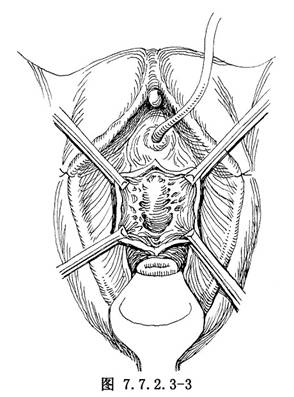

2.游离阴道前壁 切开阴道前壁的深度,应恰至露出膀胱颈及尿道后壁肌层为止,约0.3~0.5cm。创缘用组织钳提起,沿此平面向两侧剥离阴道壁,剥离范围视阴道膀胱膨出程度而定(图7.7.2.3-3)。创面大的出血应缝扎止血,渗血可用湿纱布暂时压迫止血。